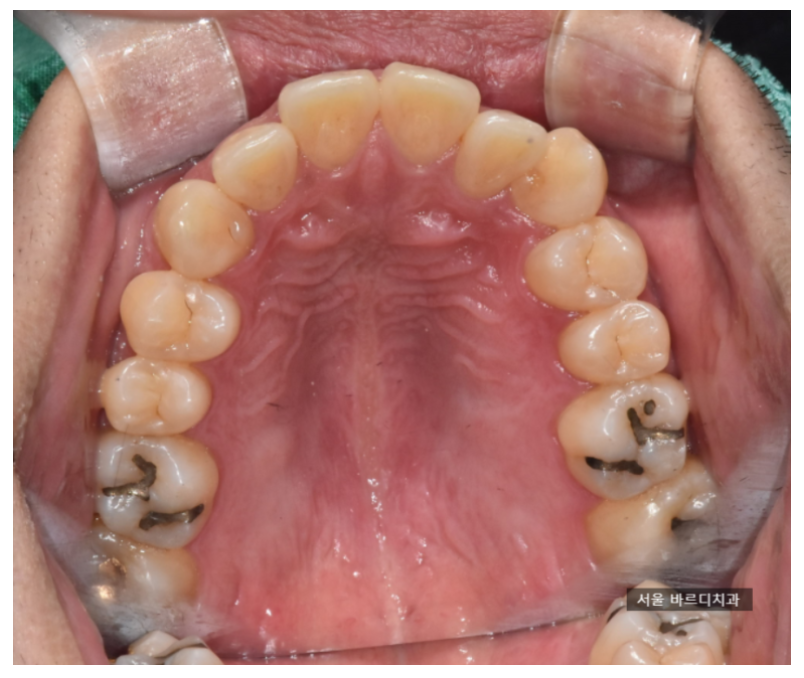

저희 병원을 오신 분들이라면

사진을 많이 찍는 것을 경험해 보셨을 겁니다.

아무리 말로 쉽게 설명드려도 한계가 있더라고요.

그래서 직접 보여드립니다.

치료 전, 후 비교 사진을 찍어서 보여드리고

최대한 자세히 설명드리는데요.